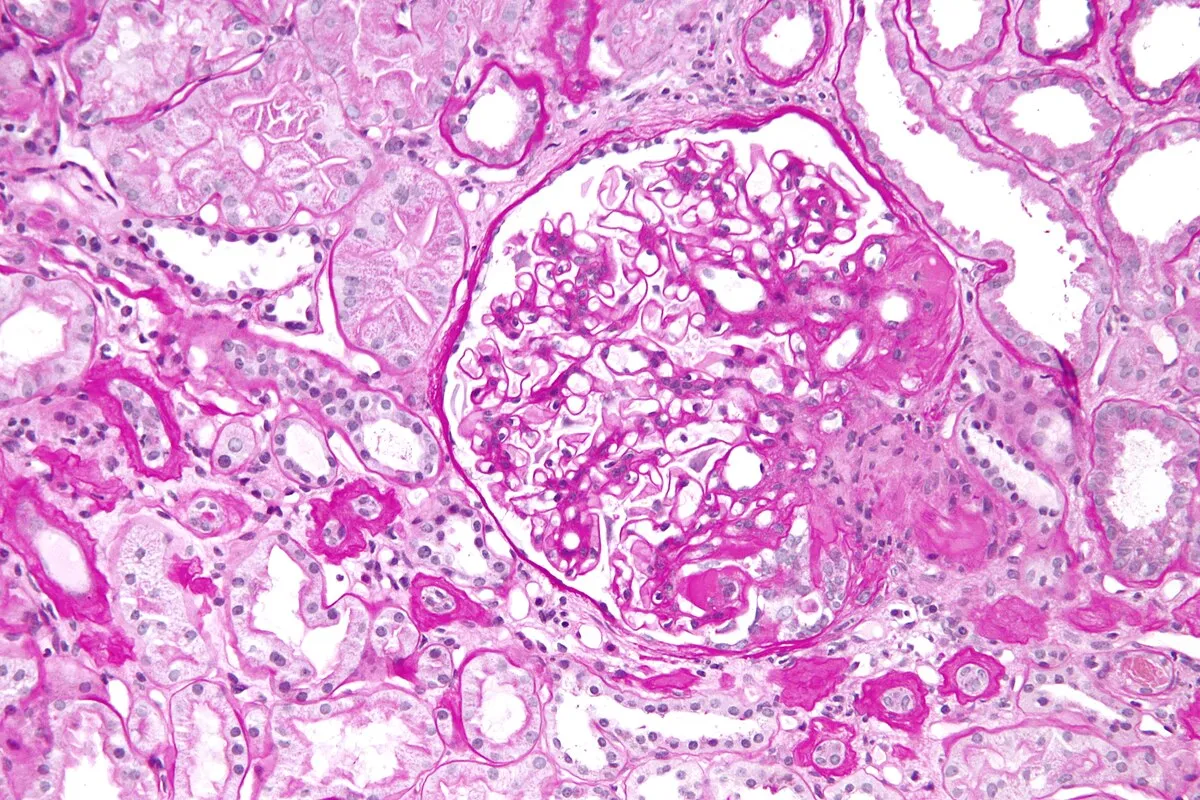

DRPAD além do Tolvaptana: Novas Perspectivas Terapêuticas nas Diretrizes KDIGO 2025

Além do tolvaptana, as diretrizes KDIGO destacam a importância de medidas não farmacológicas e abordagens complementares no manejo da DRPAD, como controle rigoroso da pressão arterial, redução de ingesta de sal e aumento de ingestão hídrica. Estudos em andamento também avaliam terapias-alvo envolvendo vias do mTOR, cAMP e inflamação. O manejo multidisciplinar permanece essencial para retardar a progressão da doença e melhorar a qualidade de vida.

Uso do Tolvaptan na DRPAD: O Que falam nas Novas Diretrizes KDIGO 2025?

As novas diretrizes KDIGO para a Doença Renal Policística Autossômica Dominante (DRPAD) atualizam os critérios de elegibilidade para o uso de tolvaptana, com ênfase na estratificação do risco de progressão rápida. O documento reforça a individualização da terapia com base em subclassificação por imagem (Mayo Clinic) e função renal. A incorporação prática dessas recomendações pode otimizar o manejo e retardar a progressão da DRC nesses pacientes.